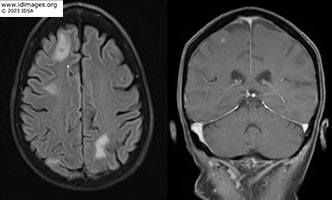

The patient suffered a fall and underwent head CT scan which demonstrated abnormalities. A subsequent MRI of the brain demonstrated numerous small ring-enhancing lesions throughout both cerebral hemispheres (Figure 3). A bronchoscopy with BAL demonstrated 97 cells, 71% neutrophils, aerobic, anaerobic, fungal, AFB, Legionella cultures, Pneumocystis jirovecii PCR and cytology were all negative. No biopsy was performed. Cell free DNA sequencing of plasma (Karius TestTM) was sent. Patient expressed preference to complete workup as an outpatient when a nodule was felt on her right calf. A new area of pain and swelling had emerged which on vascular ultrasound appeared to be an abscess. An MRI of the tibia/fibula demonstrated a 1.5x1.4cm peripherally enhancing lesion in the medial gastrocnemius muscle concerning for intramuscular abscess (figure 4). Interventional radiology performed aspiration of the abscess.

- Figure 3: MRI brain with and without contrast.

Patient treated with ceftriaxone IV 2gm every 12 hours for 3 months and sulfamethoxazole-trimethoprim 800-160mg 1.5mg tablets by mouth every 12 hours for plan of at least 12 months of therapy. Repeat CT chest 1 month (Figure 8a) and 6 months (Figure 8b) after start of antimicrobial therapy showed marked improvement in the cavitary consolidation in the right upper lobe. MRI brain after 6 months of treatment with near complete resolution of prior infection (Figure 9b).

- Figure 9: MRI brain after 6 months of treatment.